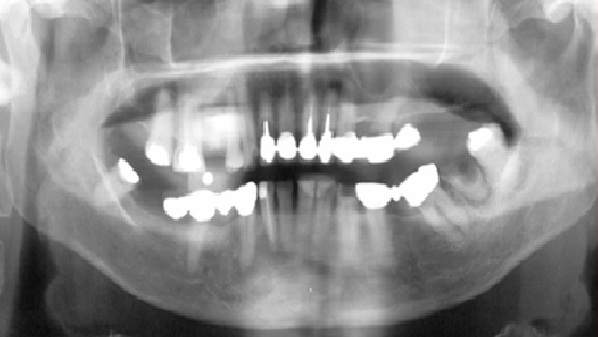

Panoramic radiograph of a female with osteoporosis showing  heavy endosteal cortical residues of the endosteal margin of the cortical bone.